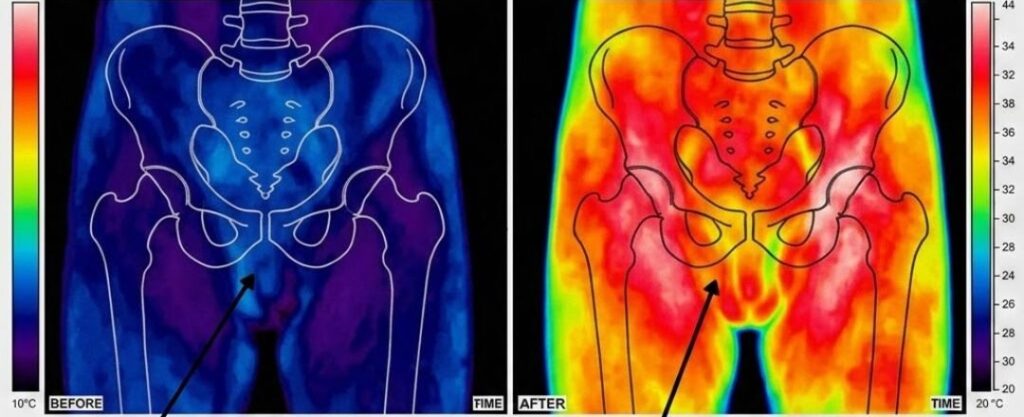

This is what happens in the cavernous nerve network of the majority of men who develop progressive erectile dysfunction after the age of 50:

The protective myelin sheath that insulates the cavernous nerve fibres begins to degrade.

This process — called progressive cavernous nerve demyelination — is silent, cumulative, and slow.

Most men don’t notice it until the damage has already become significant, because the nervous system compensates for minor degradation in ways that aren’t obviously detectable.

The brain continues to generate the arousal signal perfectly.

The desire is completely intact.

But the signal travels along a compromised nerve pathway — losing strength, losing speed, losing precision with every millimetre of degraded myelin it passes through — and arrives at the smooth muscle tissue too weakened to trigger the full relaxation response.

The blood doesn’t rush in the way it once did.

The erection is partial. Or slow. Or it starts and then fades before it’s fully there.

It is not that your body does not want to respond. It is that the message is no longer getting through cleanly. And every month that passes without addressing the underlying nerve degradation, a little more of the signal is lost in transit.

Dr. Harlow's team were testing a different hypothesis.

They were working with a protocol based on low-intensity acoustic frequency therapy — precisely calibrated sound wave pulses delivered directly to the damaged nerve tissue.

The principle, borrowed from frontier research in sports rehabilitation medicine, was that specific acoustic frequencies could stimulate mitochondrial activity in the cells surrounding damaged nerve fibres.

And that by restarting mitochondrial energy production in those cells, you could provide the biological fuel needed for myelin repair to begin.

By month seven, the data was quietly encouraging.

Several participants were showing measurable improvements in nerve conduction velocity in the treated limbs.